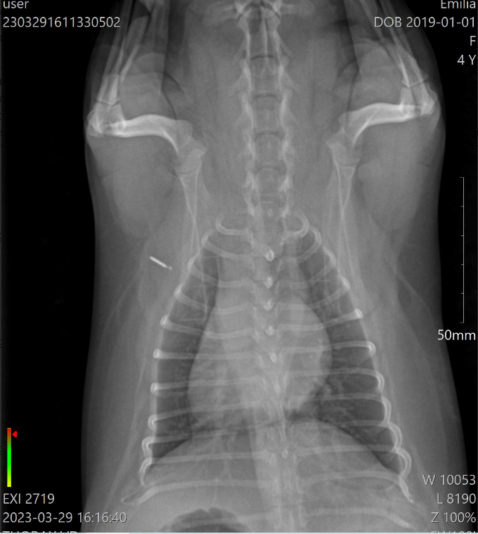

these are the photos of the bloodwork and from the ultrasound

This post is about a patient of mine that came to me on Wednesday.

General information and history: Cat, male, not castrated, 11 years old with different behaviour since 3 days. According with the owners, the cat didnt want to eat and drink for 3 days. Also he wasnt active and he was hiding. The owners didnt have…